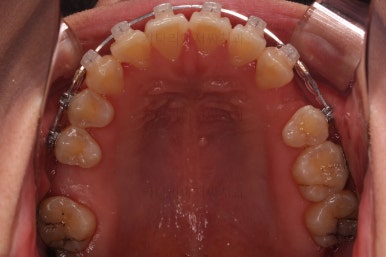

초진 시 입안의 모습입니다.

당장 눈에 띄는 부분은 아래 앞니 사이에 틈새가 있어 치석도 많이 쌓여있는 상황이고요.

윗니-아랫니를 각각 보면 치아가 썩고 부러져 뿌리만 남은 치아가 많이 보입니다.

남은 치아들도 곳곳에 충치가 보이고요.

또 전반적으로 앞니가 앞으로 밀려나와 뻐드러져 있는 모습도 관찰되네요.